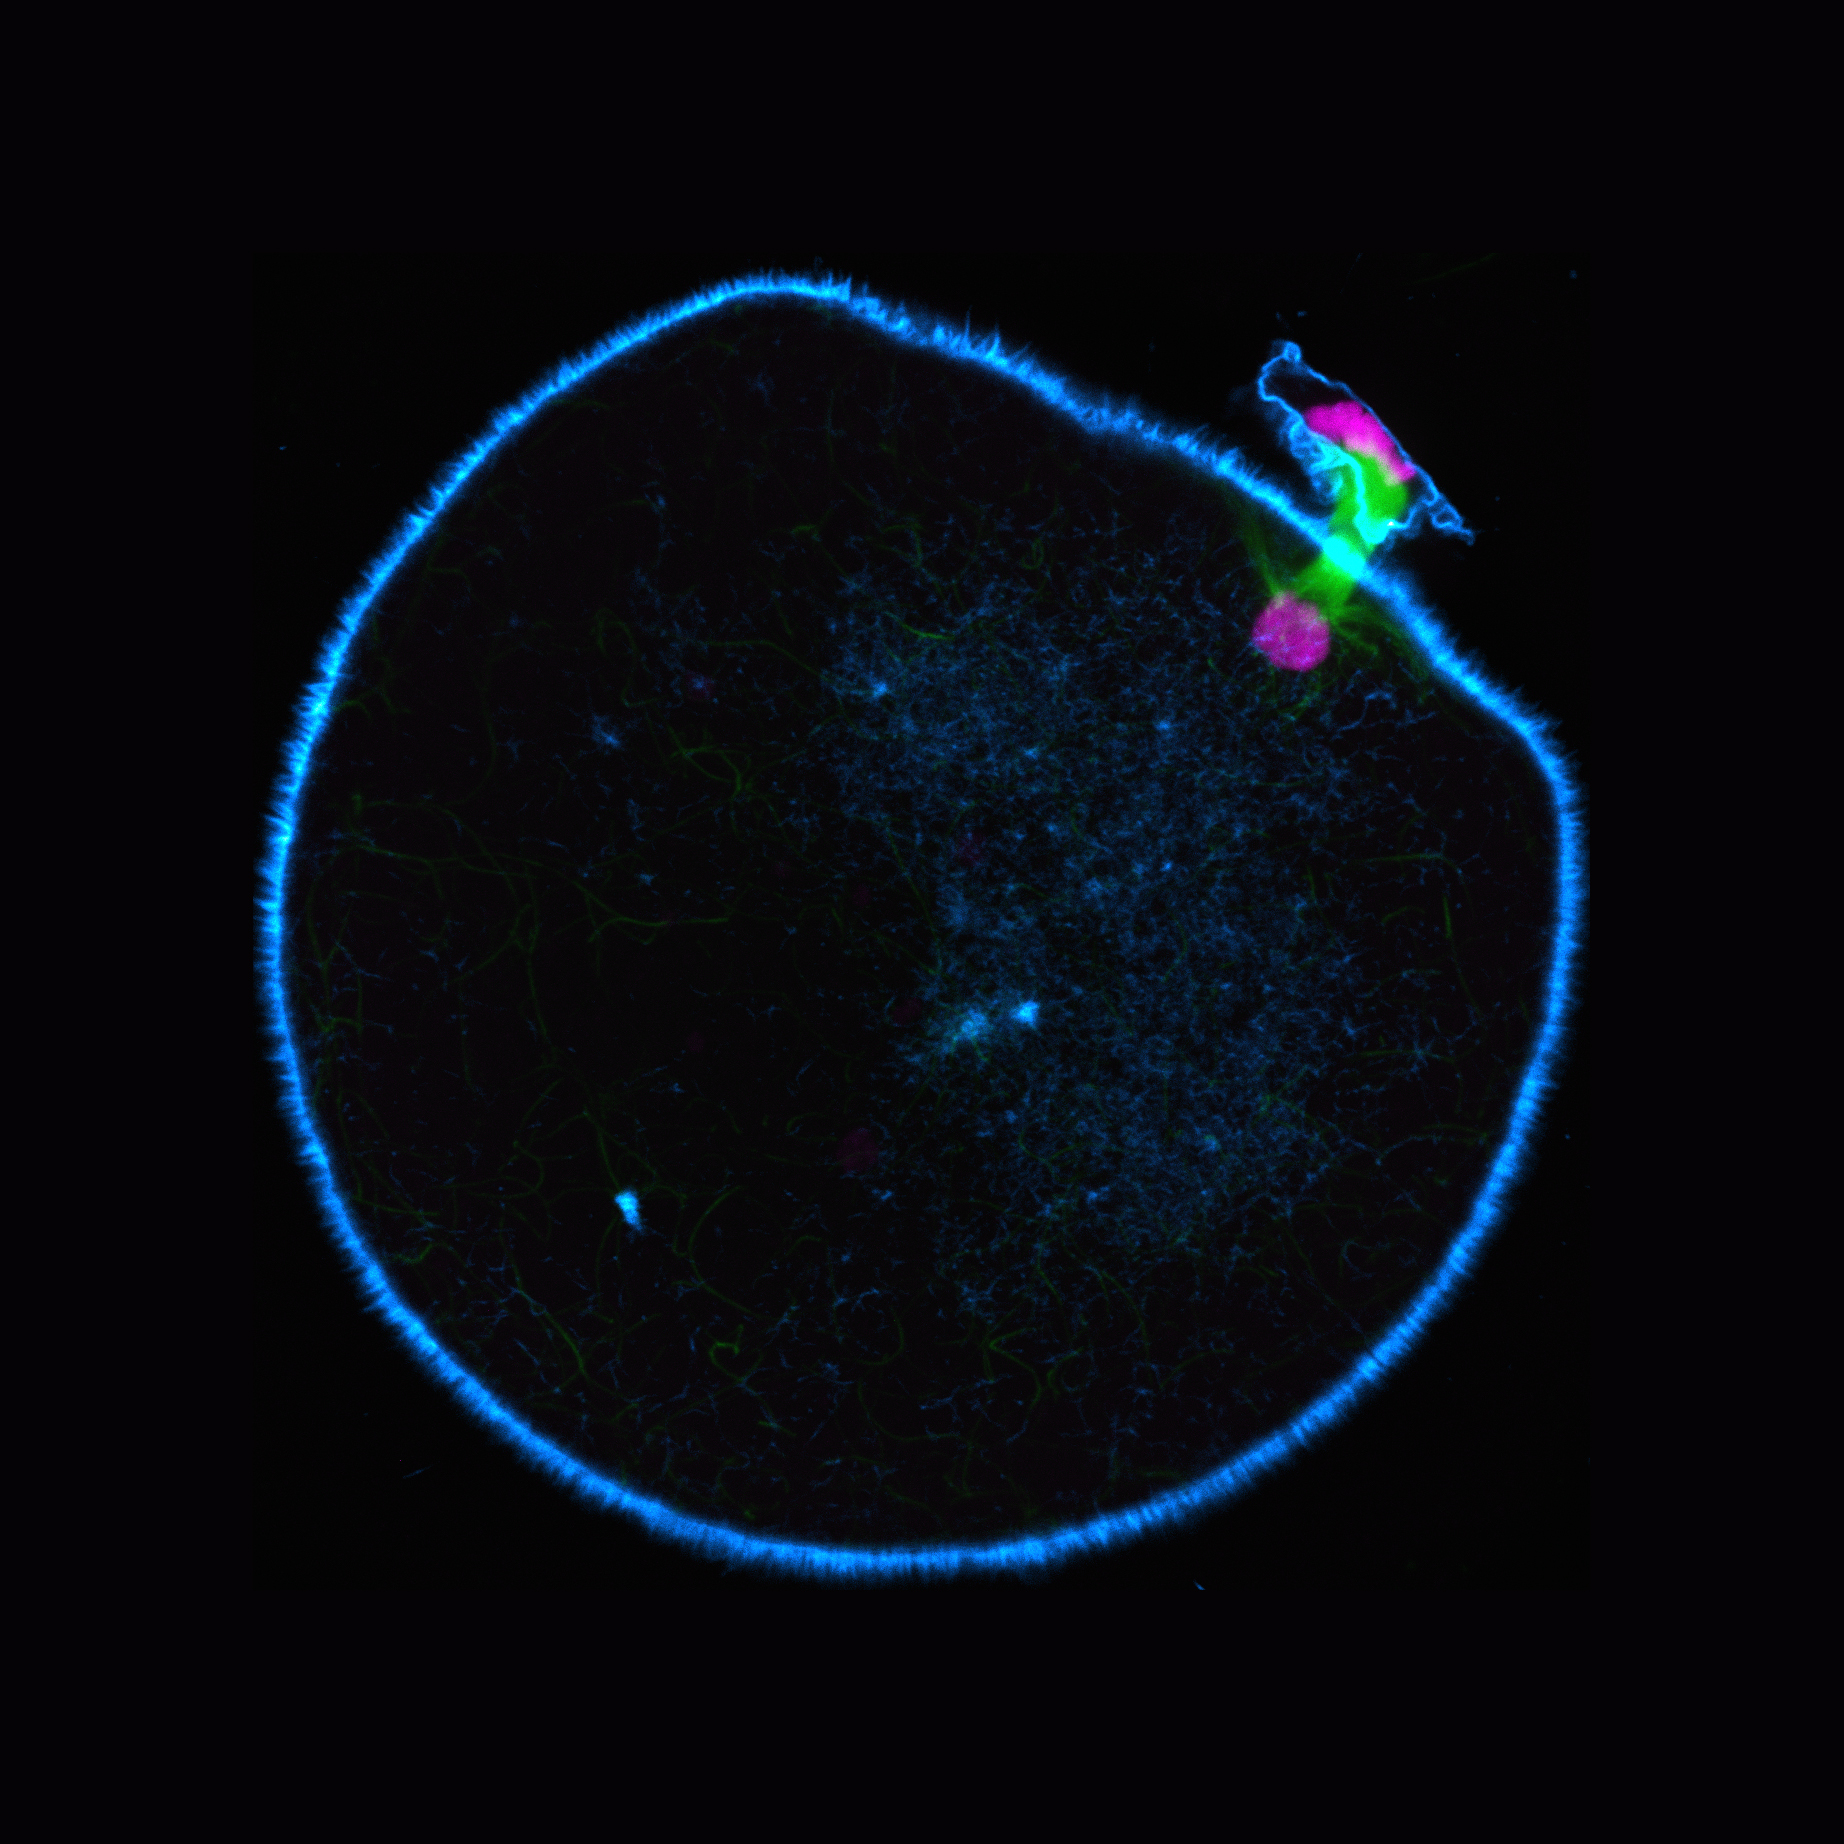

Wenn ein Spermium eine Eizelle befruchtet, ist das der Beginn eines neuen Lebens. Dann vereinigen sich die Erbinformationen (DNA) der Eltern: Spermium und Eizelle bringen je eine Kopie der 23 Chromosomen mit, die die DNA tragen. Der entstehende Embryo erhält somit einen kompletten Chromosomensatz. Die Vorläuferzelle der Eizelle, die Oozyte, besitzt allerdings zwei Kopien eines jeden Chromosoms. Vor der Befruchtung muss sie daher die Hälfte ihrer 46 Chromosomen ausschleusen. Dies geschieht, während die Zelle heranreift, in einer spezialisierten Zellteilung, der Meiose. Dabei werden die Chromosomen der Oozyten mithilfe einer komplexen Maschinerie – dem Spindelapparat – getrennt. Er besteht aus Spindelfasern, die sich während der Meiose an die Chromosomen anheften. Die Fasern ziehen dann je eine Kopie jedes Chromosoms zu den gegenüberliegenden Polen der Spindel, die Oozyte teilt sich schließlich dazwischen.

Die Wissenschaftler*innen entdeckten, dass menschliche Oozyten vergleichsweise geringe Mengen des Proteins KIFC1 enthalten. Dieses Motorprotein baut Brücken zwischen den Spindelfasern, die helfen, die Fasern richtig auszurichten und verhindern, dass sie auseinanderfallen. „Oozyten von Mäusen, Schweinen und Rindern enthielten im Vergleich deutlich mehr KIFC1-Protein“, erklärt Chun So, Postdoktorand in Schuhs Abteilung und Erstautor der Studie. Im nächsten Schritt untersuchten die Forschenden, ob die Menge des Proteins tatsächlich die Stabilität der Spindeln beeinflusst und entfernten dazu das KIFC1-Protein aus den Oozyten von Mäusen und Rindern. Möglich machte dies eine neue in Schuhs Labor mitentwickelte Methode namens Trim-Away, die nahezu jedes Zielprotein schnell aus jeder Art von Zelltyp abbaut. „Ohne das Motorprotein bildeten auch Mäuse- und Rinder-Oozyten instabile Spindeln und es kam zu mehr Fehlern bei der Chromosomentrennung. Unsere Ergebnisse legen nahe, dass KIFC1 entscheidend dazu beiträgt, Chromosomen bei der Meiose fehlerfrei zu verteilen“, berichtet der Nachwuchswissenschaftler.

Könnte KIFC1 daher ein Ansatzpunkt sein, um Fehler bei der Chromosomentrennung in menschlichen Eizellen zu reduzieren? „Für uns war die spannende Frage: Wird die Spindel stabiler, wenn wir zusätzliches KIFC1 in menschliche Oozyten einbringen“, erklärt Schuh. Unter dem Mikroskop waren in den Zellen, die zusätzliche Mengen des Motorproteins enthielten, die Spindeln deutlich intakter. Dadurch traten weniger Fehler beim Trennen der Chromosomen auf. „Das Einbringen von KIFC1 in menschliche Oozyten ist somit ein möglicher Ansatz, um Fehler in Eizellen zu reduzieren. Dies könnte dazu beitragen, Kinderwunschbehandlungen erfolgreicher zu machen“, hofft die Max-Planck-Direktorin.